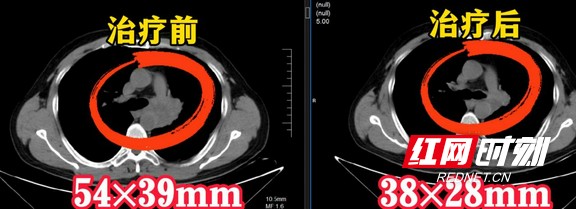

经过三周的治疗后,姚叔顺利出院了。近日,在定期复查后,姚叔肺部的肿瘤从原来的54×39mm缩小到了38×28mm,相当于缩小了一半!

患者治疗前后检查影像。